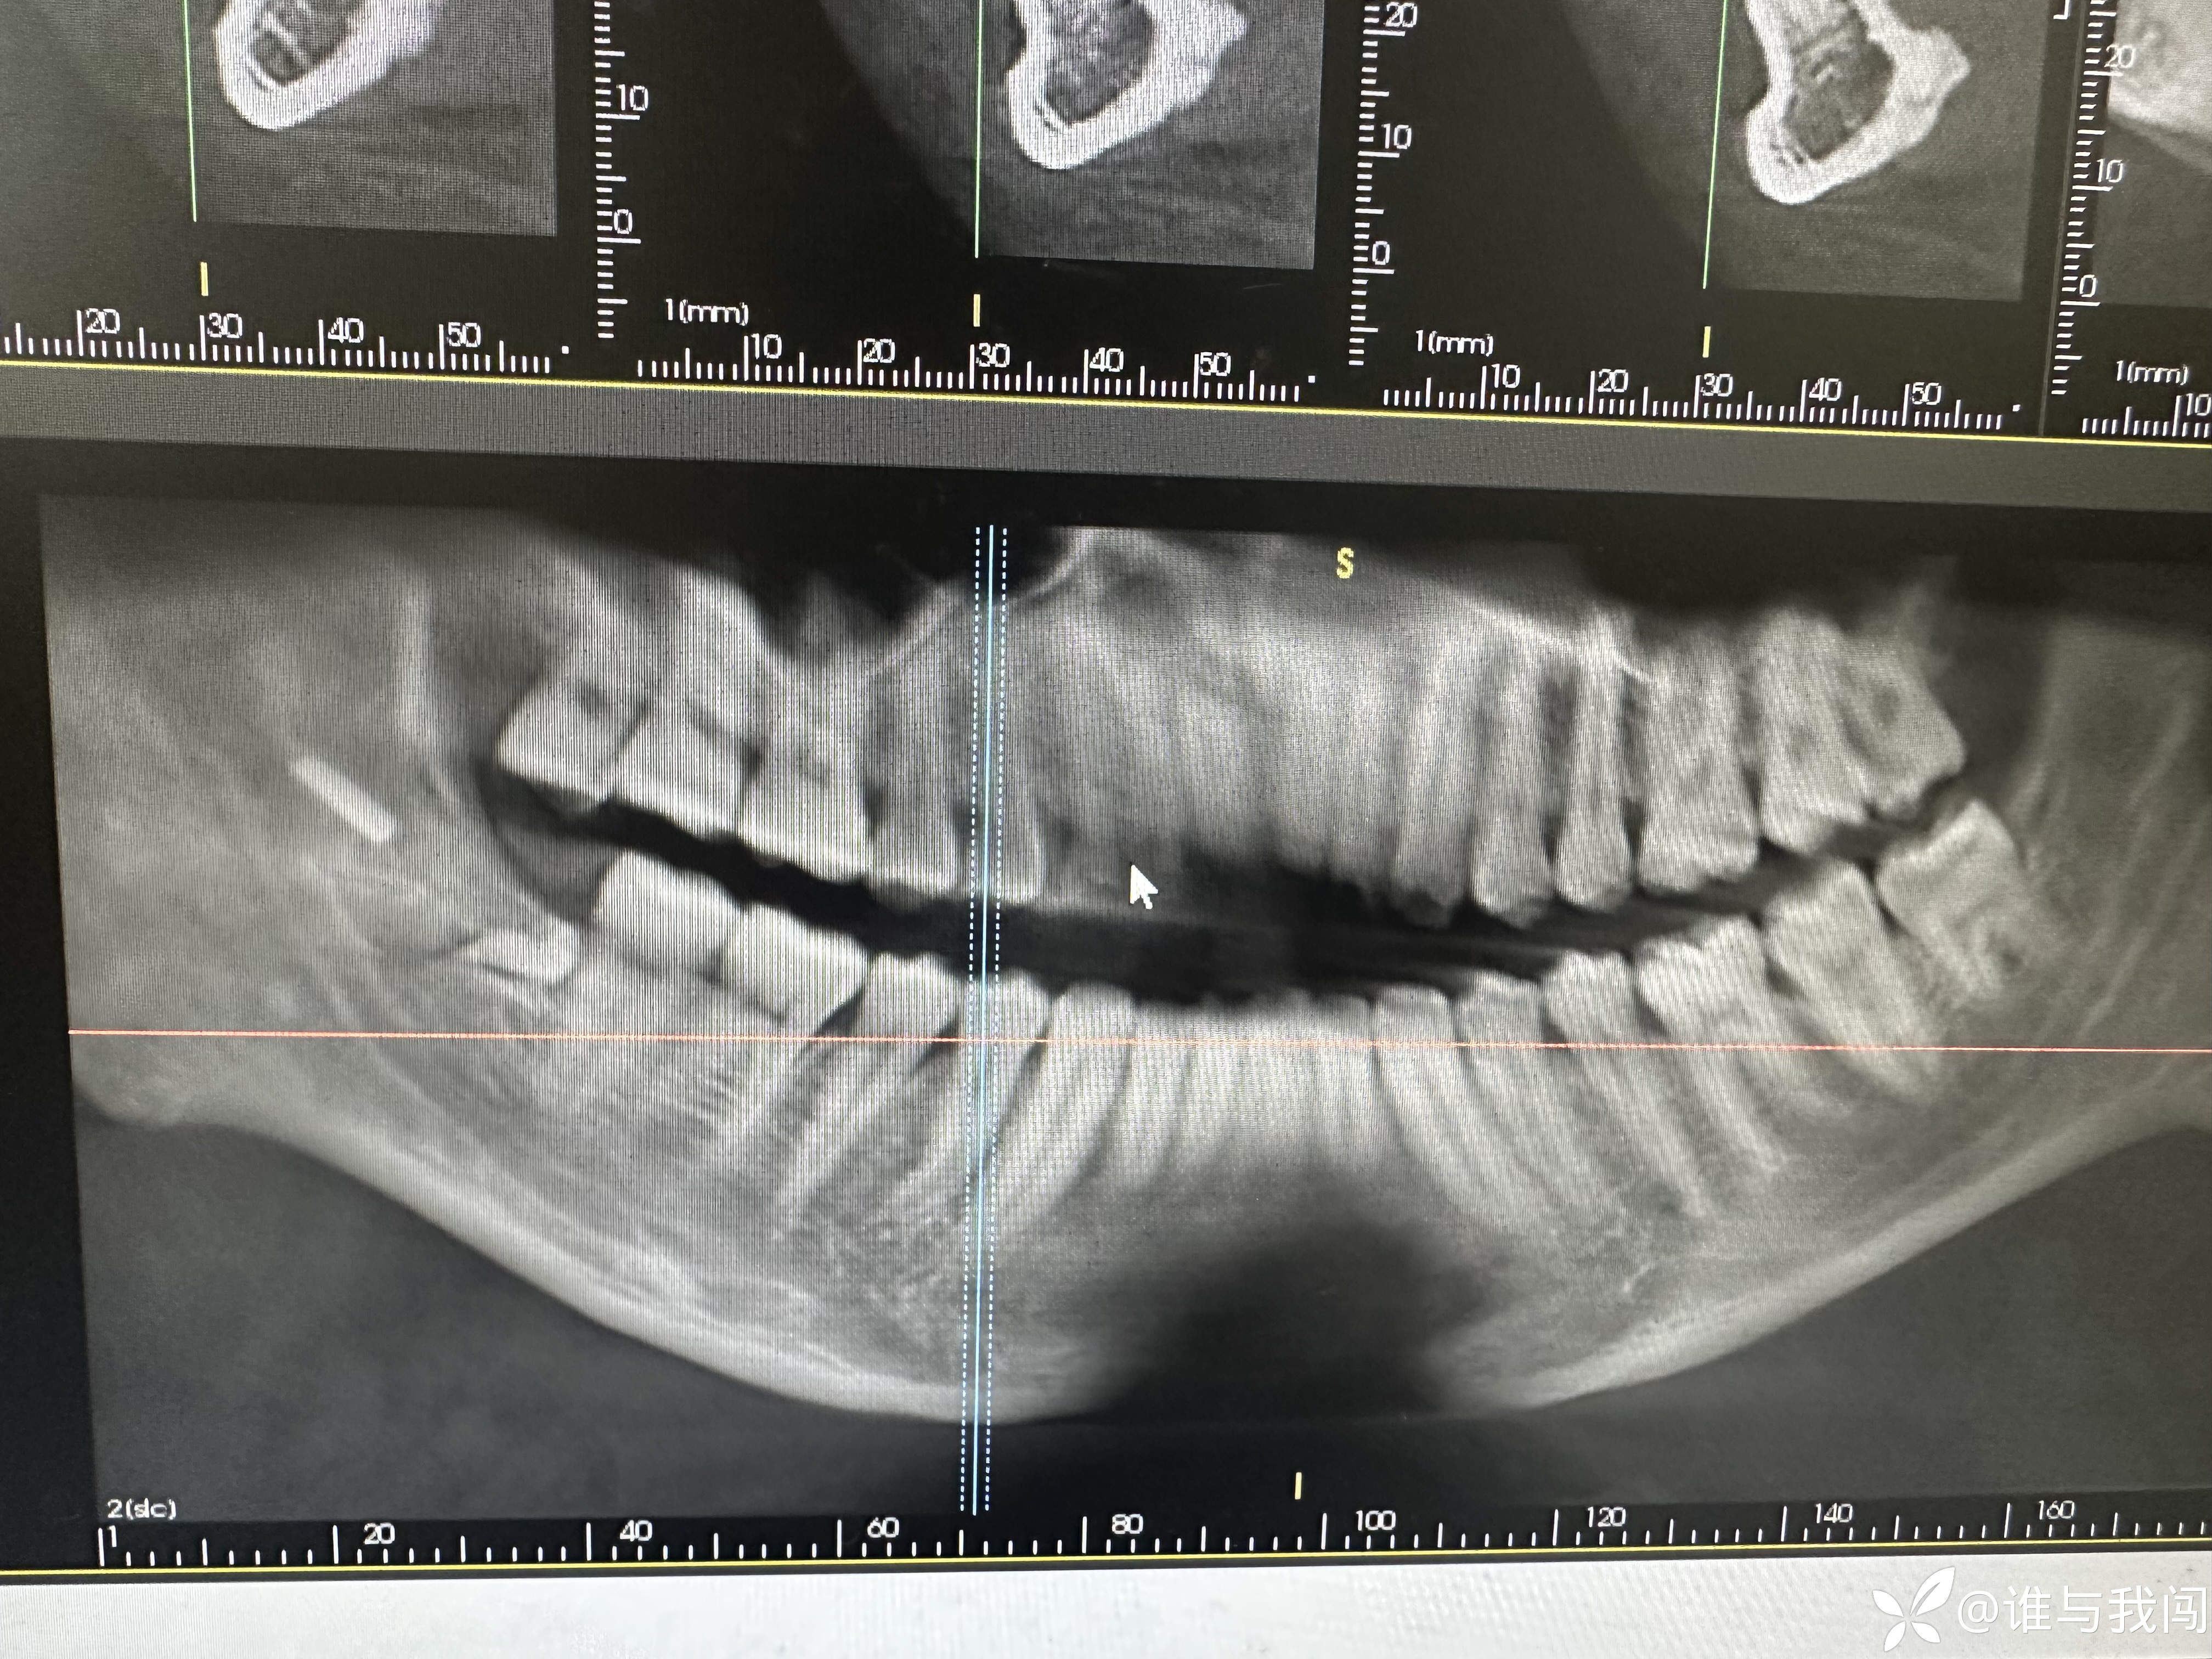

患者是从我们医院另外一个院区过来的,48阻生齿拔除,带过来的时候说是牙挺断在里面了,拍ct看有一个近9mm的样子,是另外一个院区一个老医生拔的。